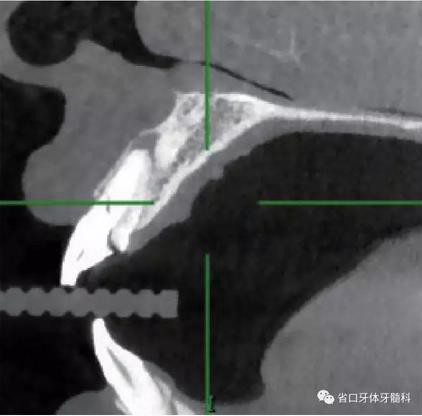

1.?病例簡(jiǎn)介 43歲女性患者,主拆:右上前牙松動(dòng)不適數(shù)日要求修復(fù)。現(xiàn)病史:患者數(shù)年前右上前牙因“齲壞”于外院行根管治療(具體不詳),數(shù)日前牙冠松動(dòng)不適,現(xiàn)覺(jué)影響咀嚼及美觀,遂來(lái)我院要求進(jìn)一步診治。否認(rèn)高血壓、心臟病等重大疾病,否認(rèn)結(jié)核、肝炎等傳染病史,否認(rèn)手 術(shù)、輸血史等,未發(fā)現(xiàn)藥物過(guò)敏。無(wú)吸煙習(xí)慣。臨床檢查:口外觀顏面基 本對(duì)稱,皮膚無(wú)紅腫破潰,顳下頜關(guān)節(jié)區(qū)無(wú)彈響、雜音、壓痛,開(kāi)口度約 37mm,開(kāi)口型“↓”,頜下、刻下和頸部未及腫大淋巴結(jié)。中位笑線??趦?nèi)檢查,口腔衛(wèi)生可,色素(+),BOP(-),PD=2mm,上頜右側(cè)中切 牙冠部變色,冠根折斷至齦下3mm,叩不適,松動(dòng)Ⅱ°~Ⅲ°。牙齦稍紅, 齦緣水平及齦乳頭高度可,屬于中厚齦生物型,附著齦寬度約5mm,唇系帶附著可。上頜右側(cè)中切牙缺牙間隙與對(duì)側(cè)同名牙一致,約>7mm,修復(fù)空 間良好。與對(duì)頜牙覆合覆蓋正常。MCT檢查示上頜右側(cè)中切牙冠根折斷至骨 下,根管內(nèi)見(jiàn)充填物,根充不全,根尖見(jiàn)陰影,大小約3mm×3mm。牙槽窩根方可用骨量可,唇側(cè)骨壁完整,冠方骨壁厚度約1mm。

圖4 術(shù)前X線片